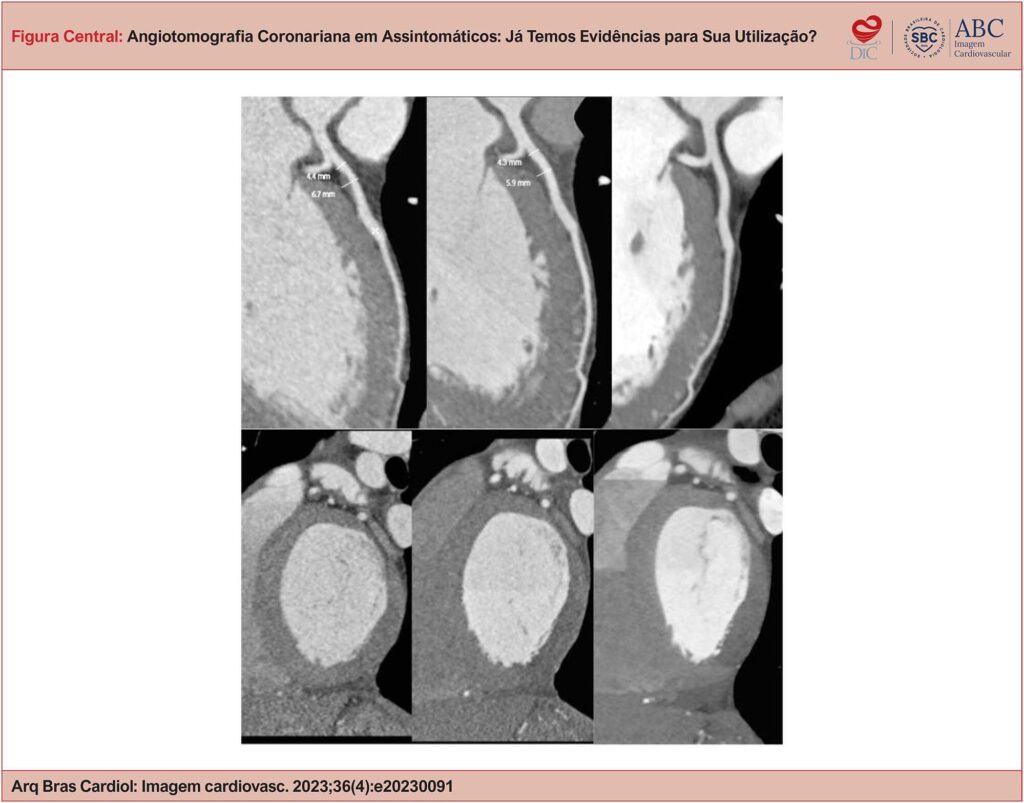

Angiotomografia Coronariana em Assintomáticos: Já Temos Evidências para sua Utilização?

As doenças cardiovasculares (CVs) são a principal causa de morte no mundo e têm manejo clínico complicado por três aspectos fisiopatológicos principais: a) longo período de instalação, com início da doença muitas décadas antes do evento clínico; b) curso clínico silencioso; c) patogênese multifatorial e heterogênea entre diferentes subgrupos humanos. A Angio TC Coronariana (ATCC) é a melhor ferramenta disponível para diagnóstico e fenotipagem da doença arterial coronariana (DAC), seja ela obstrutiva ou não obstrutiva. Isso permite o diagnóstico precoce e o acompanhamento da doença, fundamentais para decisão de quem deve ser tratado, a titulação terapêutica e o aumento da aderência ao tratamento clínico. O diagnóstico precoce e preciso em medicina geralmente resulta em melhores desfechos clínicos.